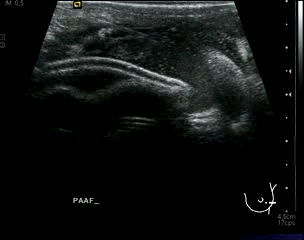

Cuando hay que extraer algún tipo de colección o seroma se puede realizar PAAF evacuadora, esa evacuación se analizará con el fin de detectar la eventual bacteria que provoque la infección, como en el caso del vídeo que está viendo, donde una cirugía mamaria ocasionó un seroma y posterior absceso infeccioso muy doloroso que hubo que extraer provocando alivio inmediato en la paciente por el efecto de presión producido.